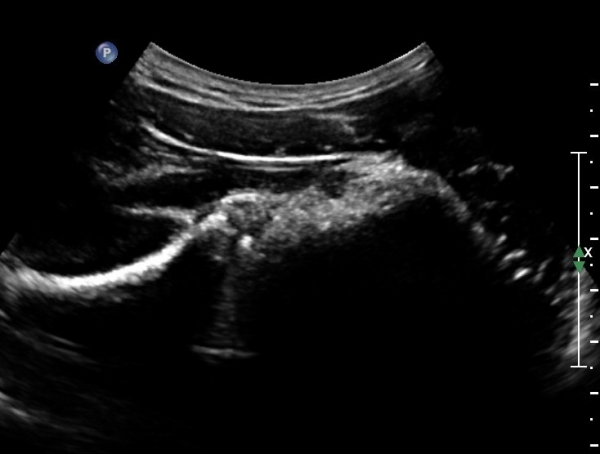

ÄÁº¤½ºÅ½ÃËÀÚ¸¦ ÀÌ¿ëÇÑ ¾î±ú µÚÂÊ È¾´Ü¸é°Ë»ç¿¡¼­ °üÀý¿Í ³»Ãø ¼ö¾× Àú·ù¿Í °üÀý¿Í¼ø ÆÄ¿­ÀÌ

°üÂûµÈ´Ù(»çÁø 3, 4, 5, 6).

ÃÊÀ½ÆÄÀ¯µµÇÏ ÈíÀÎÄ¡·á Áß ÁÖ»ç¹Ù´ÃÀÌ ¼ö¾×³»¿¡ Á¤È®È÷ À§Ä¡ ÇÑ °ÍÀÌ °üÂûµÈ´Ù(»çÁø 7).